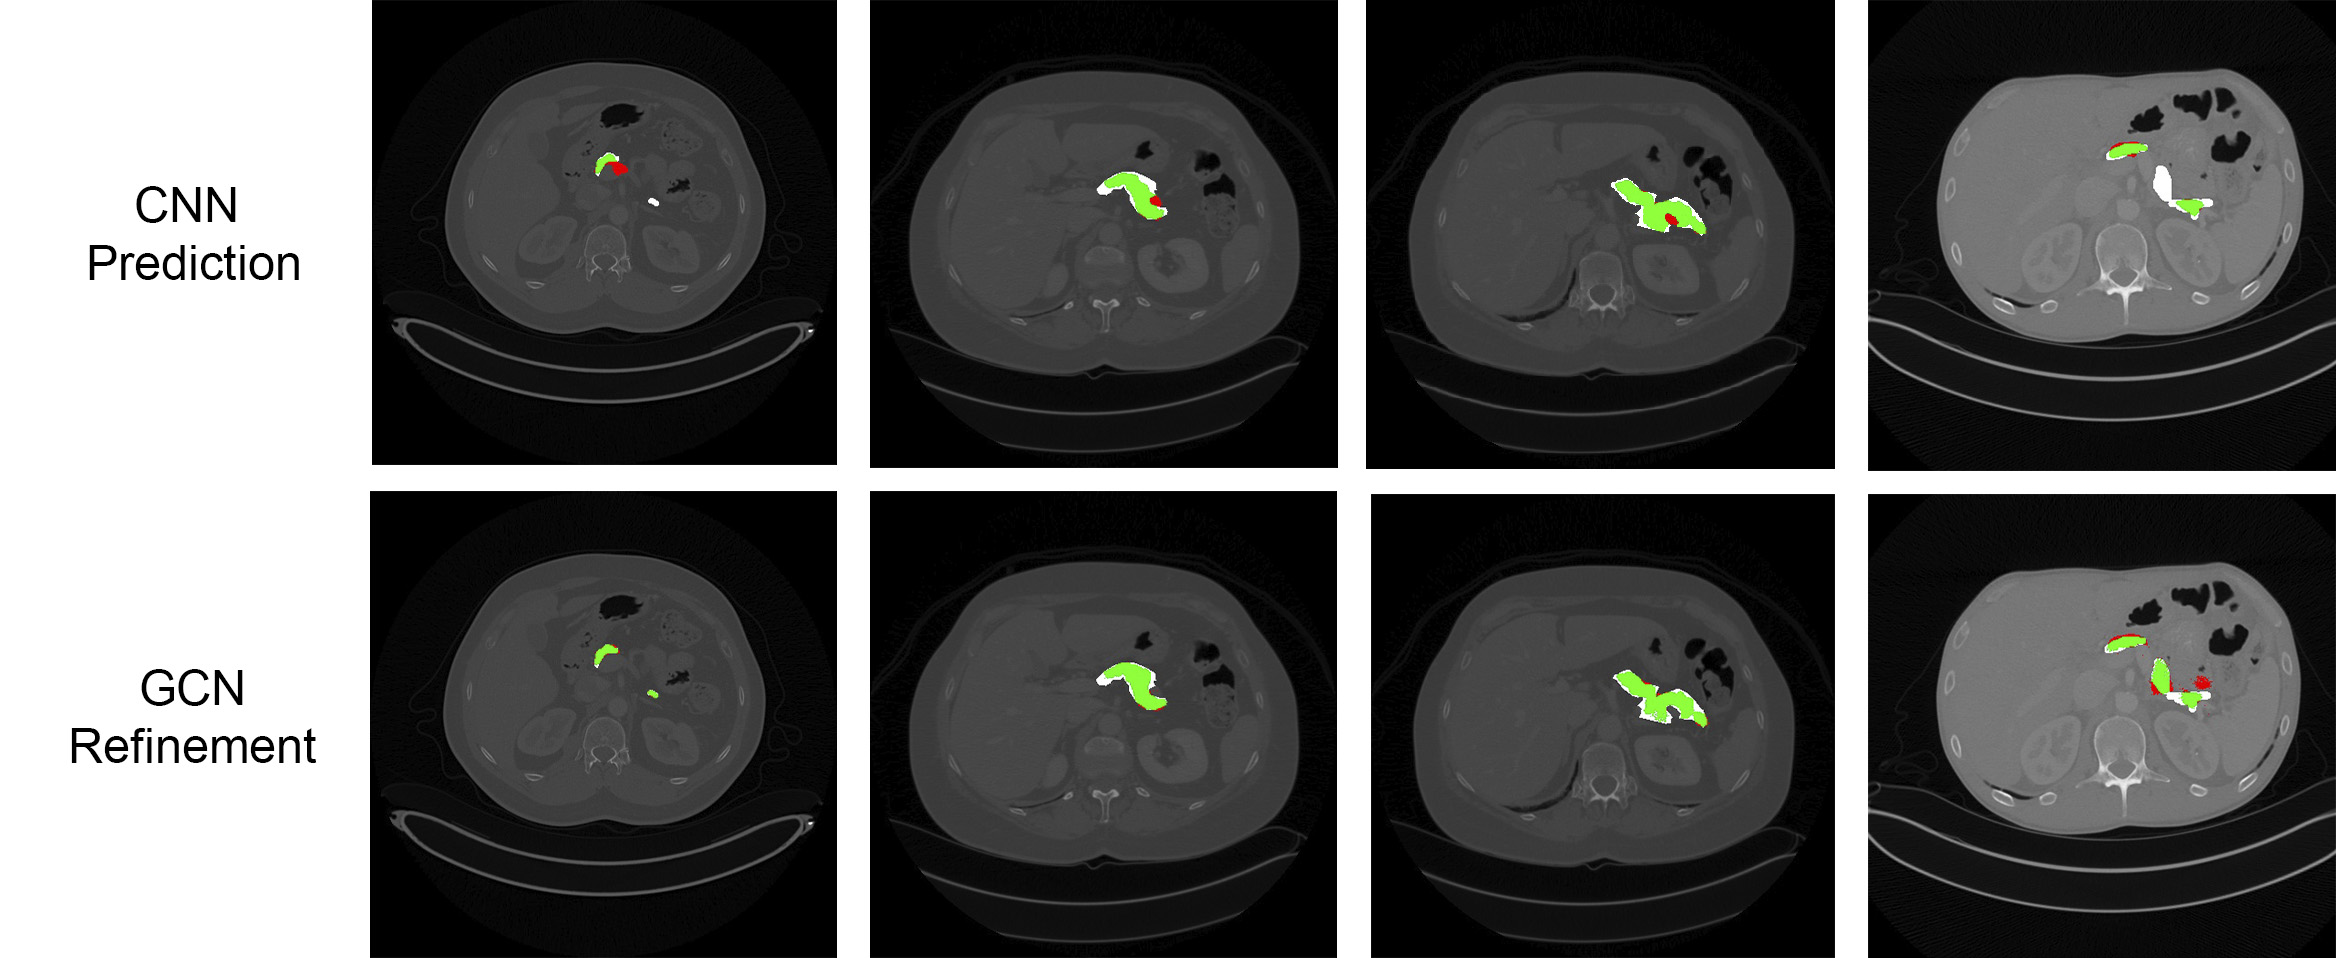

Refer to caption

Figure 3: Comparison of the CNN prediction and its corresponding GCN refinement for pancreas segmentation. Green colors indicate true positives (TP), red indicates false positives (FP), and white false negative (FN) regions. From left to right: the first column shows an FP region removed and an FN region recovered after the refinement. The second and third columns show FP regions removed. The fourth column shows an FN region recovered but also a new FP region generated.

Results are presented in Table 1. The GCN-based refinement outperforms the base CNN model and the CRF refinement by around 1% and 0.6% respectively in the pancreas segmentation task. For spleen segmentation, our GCN refinement presented an increase in the dice score of 2% with respect to the base CNN, and 1.7% with respect to the CRF refinement. Figs. 3 and 4 show visual examples of the GCN refinement compared with the base CNN prediction.